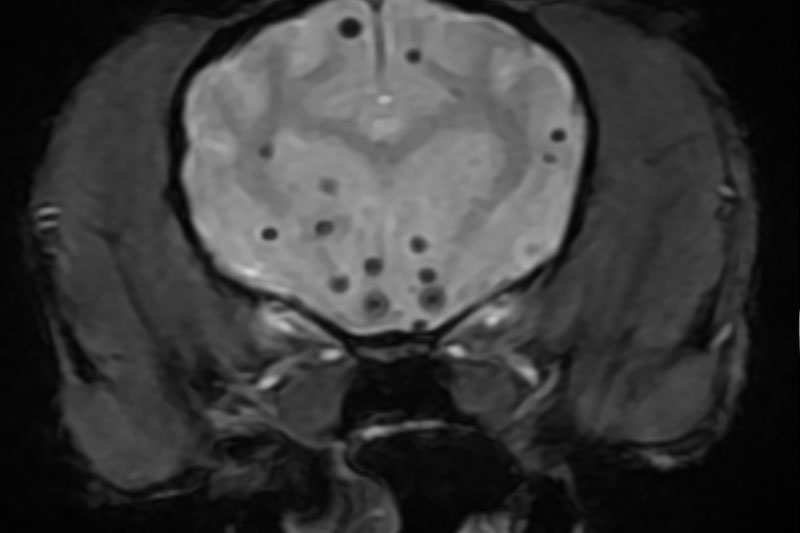

본 병원은 GE사의 1.5T 고해상도 자기공명영상장치(MRI)를 이용하여, 자기장을 이용한 비침습적 방식으로 뇌, 척수, 근골격계 등 다양한 연부조직을 정밀하게 영상화할 수 있습니다. MRI는 방사선을 사용하지 않아 반복 촬영에도 안전하며, 신경계 및 연부조직에 대한 탁월한 해상도를 제공하여 정확한 진단에 매우 유용합니다.

또한 본원의 MRI 장비는 GE사의 PROPELLER 기법을 도입하여 호흡이나 움직임에 따른 영상 왜곡을 최소화하면서도 검사 시간을 단축시켜, AI 기반 영상 처리 기술을 통해 노이즈를 줄이고 더욱 선명하고 명확한 영상을 획득할 수 있습니다. 이러한 기술적 강점을 바탕으로 마취 시간과 그에 따른 환자의 부담을 줄이면서도, 진단에 충분한 고화질 영상을 안정적으로 확보할 수 있습니다.